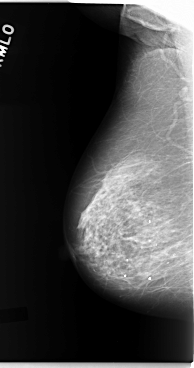

C_0093_1.LEFT_MLO

LEFT_MLO LINES 5840 PIXELS_PER_LINE 3104 BITS_PER_PIXEL 12 RESOLUTION 50 OVERLAY